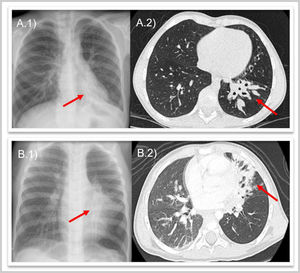

Caso 1. Varón de 8 años, sin antecedentes de interés, que presenta tos productiva de un año de evolución con atelectasia crónica del lóbulo inferior izquierdo (LII) en radiografías (RX) de tórax y bronquiectasias con engrosamiento mural y contenido mucoso en tomografía computarizada (TC) pulmonar (fig. 1). Se realiza broncoscopia flexible visualizando cuerpo extraño (CE) intrabronquial en LII que se extrae en el mismo procedimiento (fig. 2, vídeo), resultando ser una cáscara de pipa.

Caso 2. Varón de 2 años, previamente sano, con súbita hemoptisis mientras saltaba en una cama elástica. En RX de tórax presenta infiltrado paracardíaco izquierdo y en TC pulmonar lesión «mal definida» en bronquio principal izquierdo con atelectasia de língula y bronquiectasias (fig. 1). En broncoscopia flexible se visualiza CE con importante edema e inflamación de mucosa adyacente, imposibilitando su extracción (fig. 2). Tras corticoterapia y antibioterapia intravenosa, se extrae mediante broncoscopia rígida, hallando una rama vegetal.

En ninguno se sospechó aspiración de CE por ausencia de episodio asfíctico, produciendo el retraso diagnóstico y la aparición de bronquiectasias, aún presentes 5 años después (fig. 3).